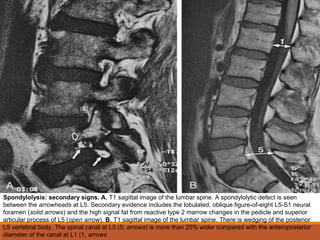

Spondylolysis: secondary signs. A, T1 sagittal image of the lumbar spine. A spondylolytic defect is seen

between the arrowheads at L5. Secondary evidence includes the lobulated, oblique figure-of-eight L5-S1 neural

foramen (solid arrows) and the high signal fat from reactive type 2 marrow changes in the pedicle and superior

articular process of L5 (open arrow). B, T1 sagittal image of the lumbar spine. There is wedging of the posterior

L5 vertebral body. The spinal canal at L5 (5; arrows) is more than 25% wider compared with the anteroposterior

diameter of the canal at L1 (1; arrows